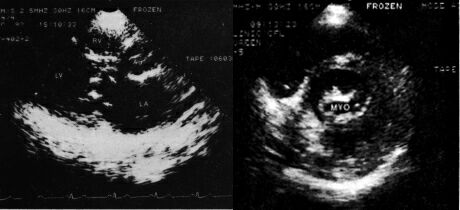

Одномерная эхолокация: признаки митрального стеноза - однонаправленное диастолическое движение створок митрального клапана, увеличение полости левого предсердия.

Двухмерная эхолокация: уменьшение площади митрального отверстия до 0.9 кв.см., уплотнение структур клапана и фиброзного кольца.